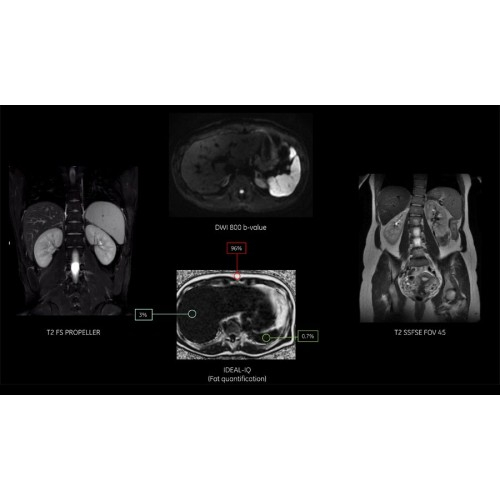

Система обеспечивает легкое сканирование, автоматическую оптимизацию протоколов, простой и автоматизированный рабочий процесс сканирования при задержке дыхания.

Снижение количества артефактов и, как следствие, уменьшение повторных сканирований.

Технологии SIGNA Pioneer позволяют проводить полное исследование брюшной полости при свободном дыхании, минимизируя артефакты движения пациента, в том числе с МР-динамическим контрастированием.